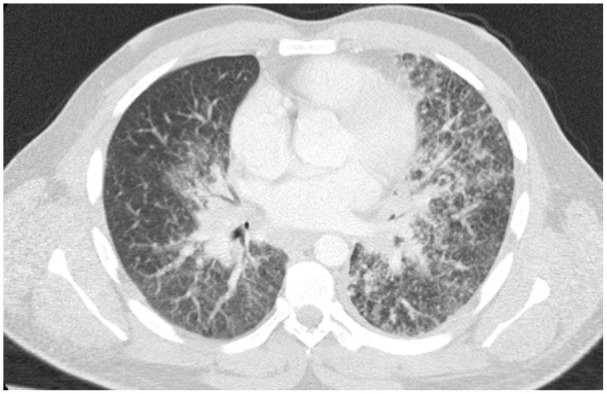

We present a case of a 42-year-old male with sarcoidosis manifesting as endobronchial mass-like lesions, a rare and atypical presentation of the disease. Sarcoidosis typically involves the respiratory system, but its occurrence as endobronchial polyps mimicking malignancy is uncommon. The diagnosis was confirmed through bronchoscopy and biopsy, revealing non-caseating granulomas. Treatment with corticosteroids led to significant clinical improvement. This case underscores the importance of considering sarcoidosis in the differential diagnosis of endobronchial masses and the role of biopsy in confirming the diagnosis.